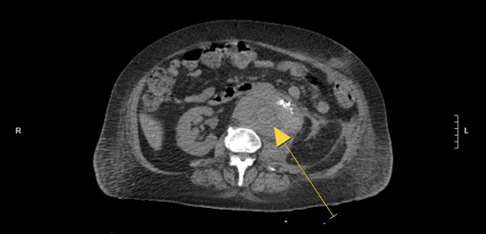

The computed tomography (CT) scan revealed a medial retrorectal mass extended to the perineal region, roughly oval, with cystic, calcium, and soft tissue components, measuring 98×97×83 mm, pushing forward the rectum and the anal canal. This mass included the 4th and 5th sacral vertebrae and the coccyx without bone lysis, with a doubt on a periosteal reaction of the coccyx (Figure 2).

Figure 2: Pelvic CT axial view with (B) and without contrast (A): Retrorectal mass with cystic, calcium, and soft tissue components, extended to the perineal region, pushing forward the rectum and the anal canal.